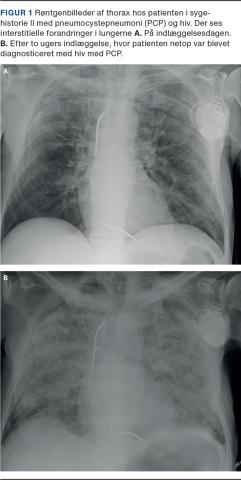

II. En 71-årig mand, som havde kronisk obstruktiv lungesygdom (KOL) og iskæmisk hjertesygdom, blev indlagt på en lungemedicinsk afdeling på mistanke om COVID-19. Han var igennem mange måneder blevet tiltagende træt, appetitløs og afkræftet og var nærmest bundet til sengen. Han havde hypoksi med en saturation på 92% og det parakliniske billede med lymfocytopeni, et CRP-niveau på 37 mg/l, anæmi, et LDH-niveau på 296 E/l og en røntgenundersøgelse af thorax (Figur 1), hvorpå der sås interstitielle forandringer, henledte mistanken på COVID-19. Trakealsekretet blev undersøgt, og han blev podet i alt fire gange for SARS-CoV-2. Alle test var negative. Hans tilstand forværredes under indlæggelsen, han blev delirøs og febril, hostede og fik progredierende behov for ilt. Han blev sat i bredspektret antibiotisk behandling uden effekt, udredt for KOL-eksacerbation og akut myokardieinfarkt uden ST-elevation, og der var mistanke om en underliggende malign tilstand. Efter to ugers indlæggelse blev PCP overvejet som differentialdiagnose, og polymerasekædereaktionstest for pneumocyster på trakealsekret var positiv. Efter konference med en infektionsmedicinsk afdeling blev udført hiv-kviktest, der udkom positiv. Patienten blev overflyttet til en infektionsmedicinsk afdeling, hvor der blev iværksat behandling for PCP og hiv. CD4-tallet var 14 celler/µl.